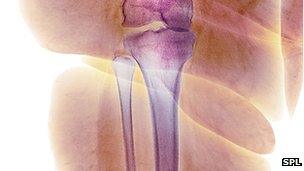

Obesity may be a risk factor for the frail bone disease osteoporosis, a study suggests.

US researchers have discovered that some people who are overweight have hidden fat inside their bones that could make them weak and prone to fractures.

The bone marrow is where the cells responsible for new bone formation - osteoblast cells - live.

Dr Bredella reasons that if more of the marrow is taken over by fat cells then this will weaken the bones.

She said: "If you have a spine that's filled with fat, it's not going to be as strong.

Bone marrow fat has been found in higher-than-normal levels in people who have osteoporosis.